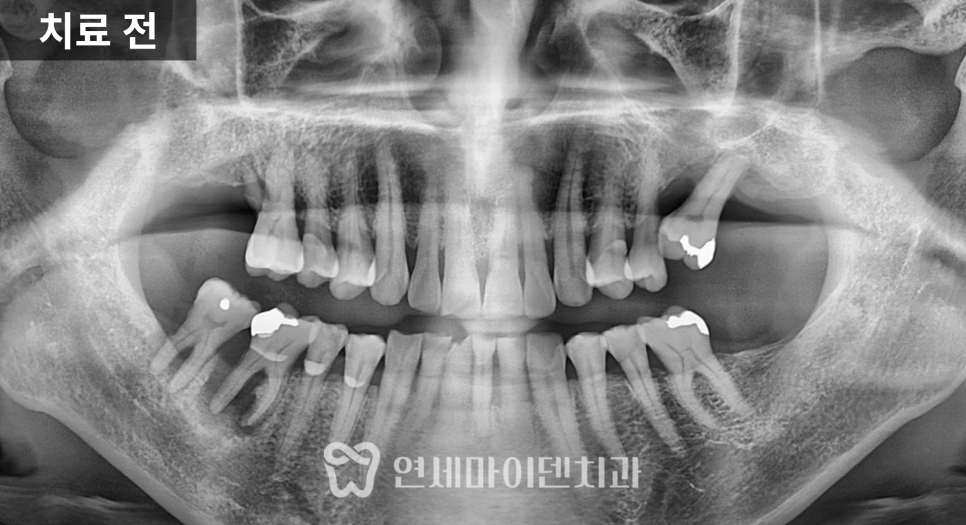

이번 케이스는

잇몸이 자주 붓고 출혈이 있으며,

고름이 반복되는 상태였습니다.

아래 어금니 한 부위

이미 크게 파절되어 있었고,

주변 잇몸에는

치석과 염증이 많이 축적되어 있었습니다.

이런 경우 해당 치아는

기능적으로 유지가 어렵고

염증의 중심이 되는 경우가 많습니다.

인접한 치아들을 확인해보니

약간의 흔들림은 있었지만,

치주 치료와 관리가 병행된다면

충분히 유지 가능한 상태였습니다.

이 경우 중요한 판단은

“살릴 수 있는 치아를 어디까지 남길 것인가”입니다.

결과적으로

염증이 심한 두 개의 치아는 발치를 결정했고,

나머지 치아는 잇몸 치료를 통해

유지하는 방향으로 계획했습니다.